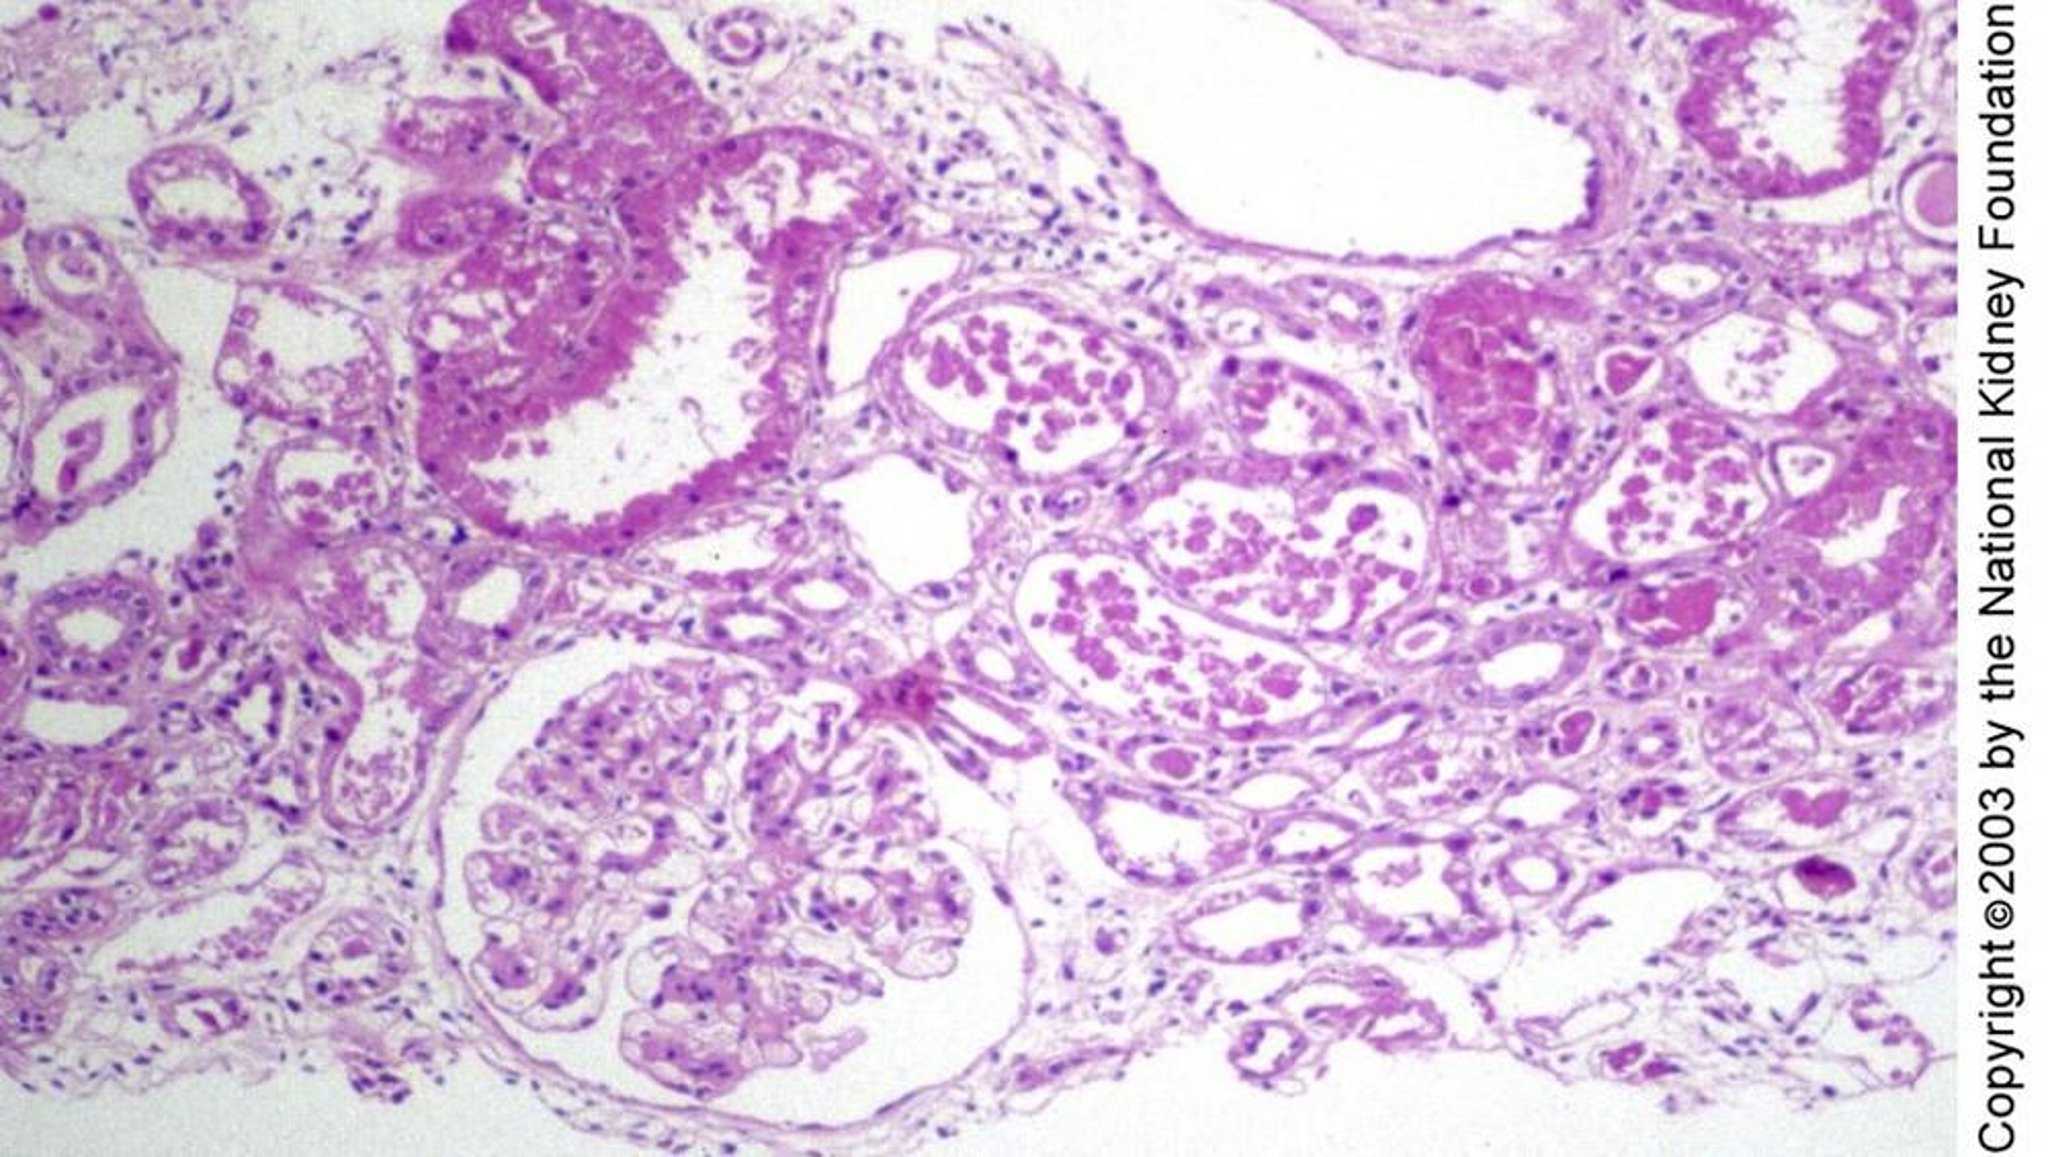

Necrosis tubular aguda

La lesión tubular en la necrosis tubular aguda puede manifestarse histológicamente como epitelio tubular aplanado en vías de regeneración sin necrosis, como se ve a la derecha del glomérulo, vacuolas y degeneración celular individual, como en la parte superior izquierda, o necrosis franca, como en el centro de la imagen (tinción de ácido peryódico de Schiff, ×100).

Image provided by Agnes Fogo, MD, and the American Journal of Kidney Diseases' Atlas of Renal Pathology (véase www.ajkd.org).